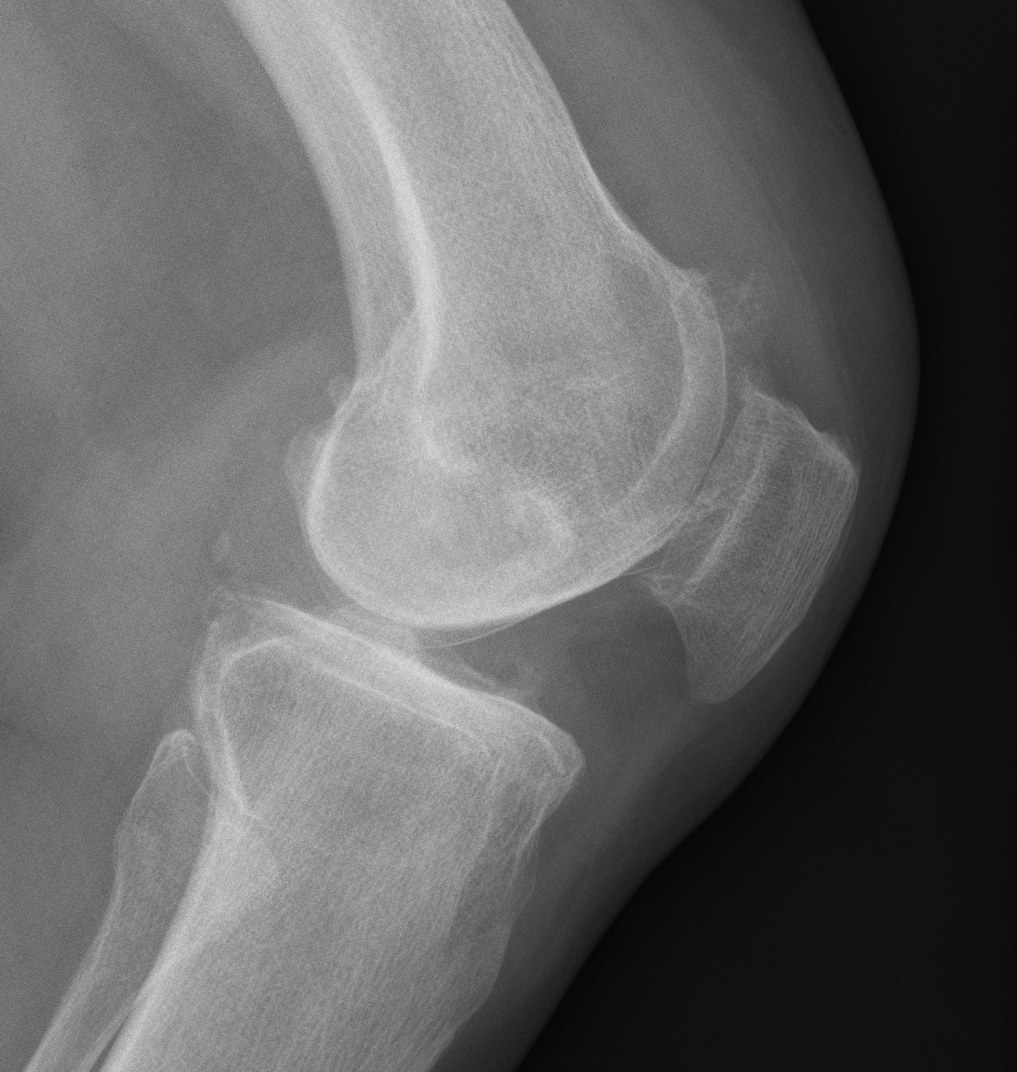

X-rays

AP / Lateral / Skyline

Patient 1